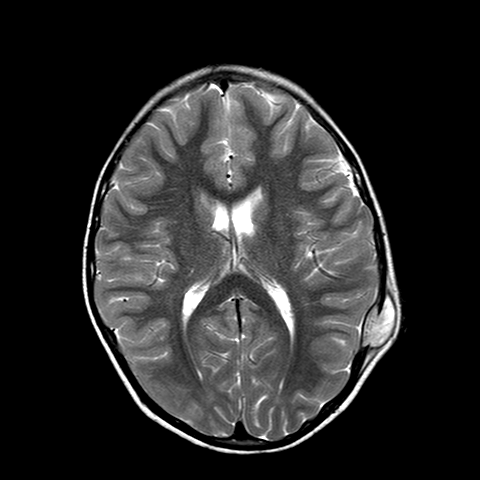

A. � un bambino di 7 anni che giunge in PS per la comparsa di una tumefazione molle in sede parietale sinistra associata a intenso dolore locale ed irritabilit� da alcuni giorni. In anamnesi trauma cranico 15 giorni prima senza sintomi associati. A. � in buone condizioni generali e l'obiettivit�, compresa quella neurologica, � nella norma. Anche gli esami ematici risultano nella norma. Vista la clinica e la storia di trauma cranico, eseguiamo TC cranio che mostra: �in sede extra-assiale parietale sinistra, apprezzabile sottile aspetto tenuemente iperdenso di larghezza 17 mm e spessore 5 mm; in corrispondenza, area tondeggiante di osteolisi di 10 x 10 mm a margini netti, con tumefazione delle parti molli extracraniche�. Per approfondimento diagnostico, eseguiamo RMN cerebrale che evidenzia: �formazione a densit� intermedia di diametro 4 x 2,5 cm in sede parietale sinistra che si localizza su entrambi i versanti del tavolato cranico, a ridosso dell'area di osteolisi.� In considerazione del reperto neuroradiologico, dopo consulenza Oncologica e Neurochirurgica, viene posto sospetto diagnostico di granuloma eosinofilo. Eseguite Rx torace ed eco addome che hanno escluso un possibile coinvolgimento viscerale. A. � stato quindi sottoposto ad intervento di curettage chirurgico che ha dato conferma istologica della diagnosi.